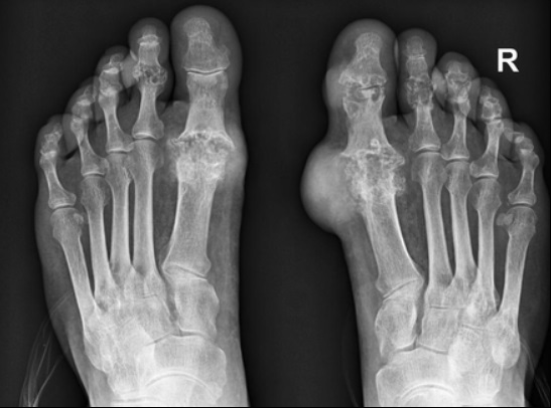

그 후, 손, 무릎, 발목의 관절에 계속해서 영향을 줄 수 있습니다. 통풍의 증상은 시기에 따라 고요산혈증, 급성 통풍성 관절염, 간헐성 통풍의 3단계로 분류할 수 있습니다. 일반적으로 엄지발가락 관절의 갑작스러운 종창이 처음 징후이며, 곧 해당 부위에 극심한 통증과 발적이 뒤따릅니다. 관절이 뜨거워져 신발을 신을 수 없게 될 수 있습니다. 그리고 손, 무릎, 발목의 관절에도 연속적으로 영향을 미칠 수 있다.

통풍이 진행된다면 10일 정도 지속되며 완화되더라도 재발하거나 악화될 수 있으므로 치료를 받아야 합니다. 급성 통풍성 관절염은 보통 엄지발가락에 나타나지만 발 관절, 발목, 무릎, 심지어 손목에도 영향을 미칠 수 있습니다. 간헐성 통풍은 일반적으로 6개월에서 2년 사이에 2번째 발작을 일으킵니다. 통풍 발작을 치료하지 않으면 시간이 지남에 따라 여러 관절로 전이될 가능성이 높아지므로 반드시 치료를 받고 정상적인 요산 수치를 유지해야 합니다.